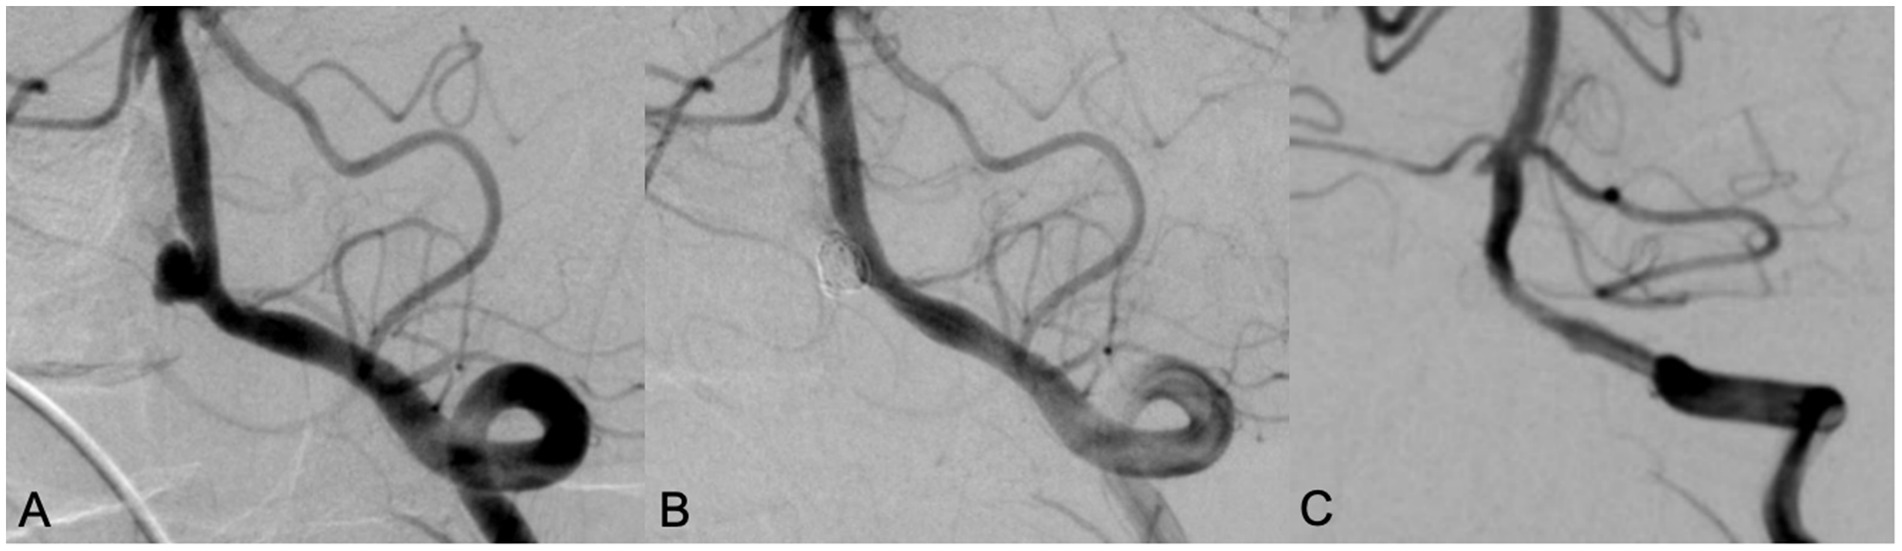

All patients successfully completed SAC for WNIA, and the technical success rate was 100%. Immediate postembolization angiography showed that in the Neuroform Atlas group, 22 aneurysms (81.5%, 22/27) achieved MRRC Class I, 5 aneurysms (18.5%, 5/27) achieved Class II, and 0 aneurysms (0%) achieved Class III. In the LVIS group, 25 aneurysms (73.5%, 25/34) achieved MRRC Class I, 9 aneurysms (26.5%, 9/34) achieved Class II, and 0 aneurysms (0%) achieved Class III. There was no significant difference in the initial obliteration class between the two groups (p = 0.549) (Table 2). Representative cases of the Atlas group and LVIS group were shown in Figures 1, 2, respectively.

Figure 2. A 70 years old male patient with headache for 5 years. DSA showed a wide neck aneurysm in the V4 segment of the left vertebral artery (A). LVIS stent was used in assisting coil embolization. Immediate angiography showed the aneurysm was completely occluded, with MRRC grading 1 (B). Angiography performed in 10 months’ follow-up showed that the aneurysm was occluded well with MRRC grade 1, but there was mild in-stent stenosis (C).